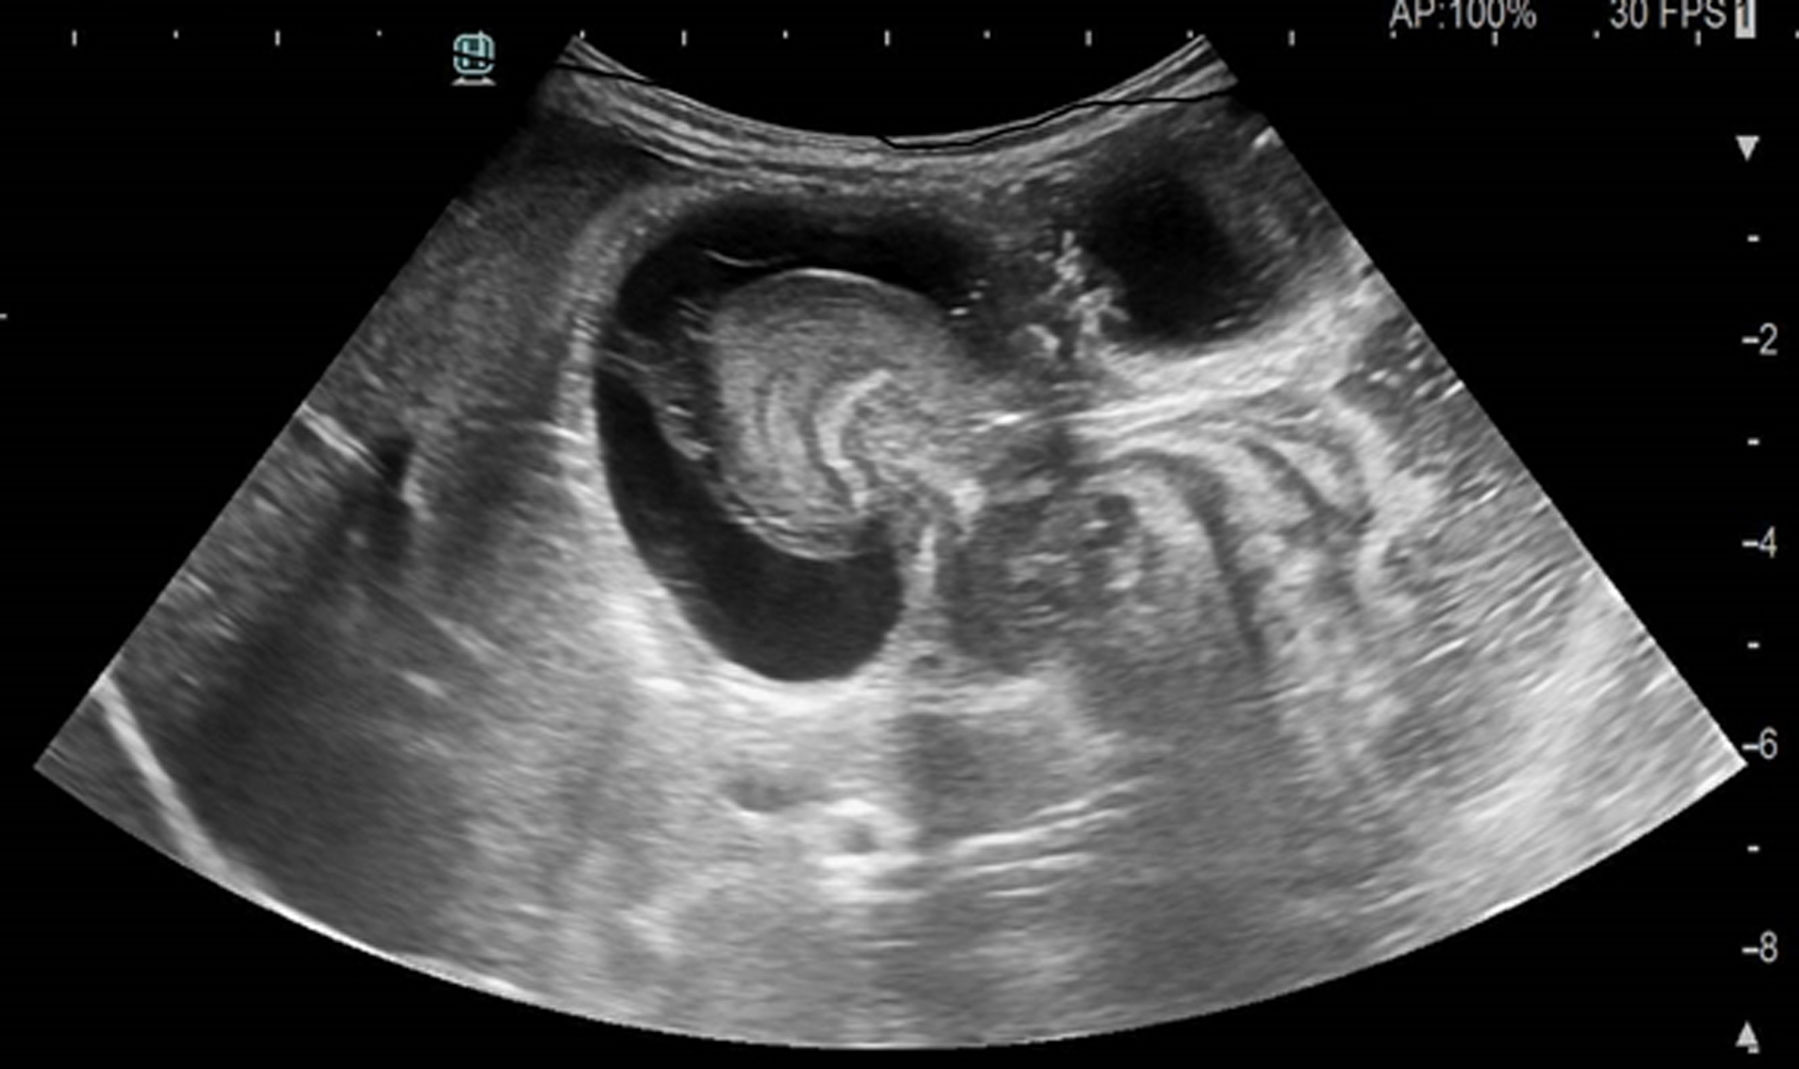

The mass was evaluated with an abdominal ultrasound scan (Fig. 1), leading to diagnosis of advanced ileocecal intussusception and possible bowel perforation.